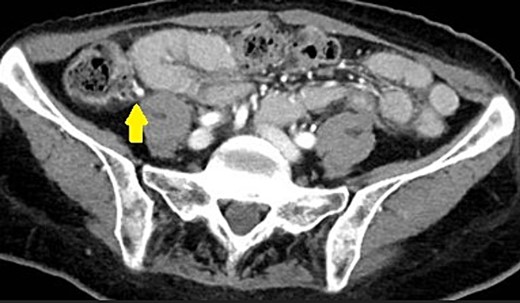

Upon arrival, she was non-toxic in appearance. She was afebrile and her blood pressure was 195/83 mmHg and lowered to 150’s/80’s with pain control in the ED. Vital signs were otherwise stable. Abdomen was soft and non-distended and had a positive McBurney’s sign. There was exquisite RLQ tenderness to palpation. Other physical exams were normal. A urinalysis, complete blood count, and complete metabolic panel were unremarkable. White blood cell count was 5800 per microliter. A computed tomography (CT) scan (Fig. 1) was obtained and showed appendicitis with an appendicolith.

CT scan demonstrating an appendicolith (proven by pathology to be fecalith) at the base of the appendix.

Piperacillin plus tazobactam for suspected appendicitis and ondansetron for nausea were initiated. She was taken for a laparoscopic appendectomy. The appendix was inflamed but not perforated, adhered to the lateral aspect of the ascending colon, and contained an appendicolith. The bowl and mesentery within the pelvis had chronic changes consistent with radiation enteritis. A gastrointestinal anastomosis stapler was used to divide the base of the appendix. A harmonic scalpel then freed the attachments. There were no intraoperative complications. The pathological specimen was confirmed appendicitis and periappendicitis with fecalith. It measured 4.6 cm long × 1.5 cm diameter with a lumen up to 0.5 cm.